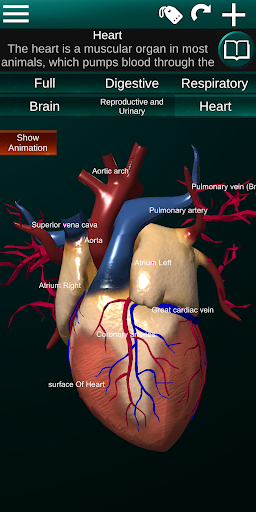

* Серце, що включає передсердя, шлуночки, аорту і одушевлення цього органу.